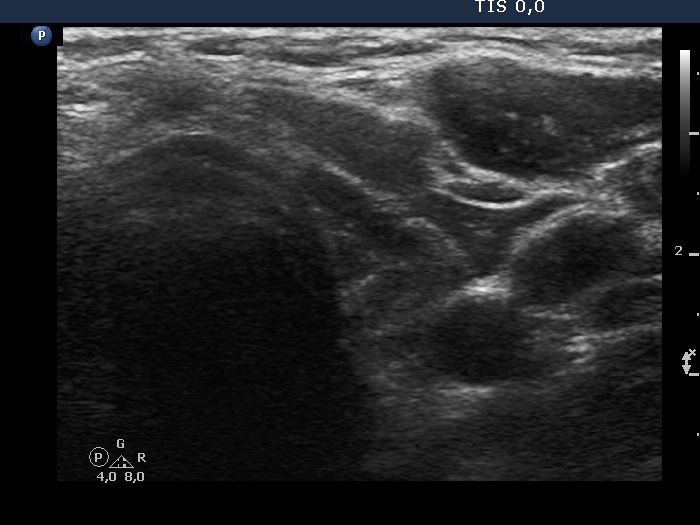

Ultrasonography. The pattern was essentially the same. The only difference concerned the lesion in the dorsal part of the right lobe which clearly increased in size. Moreover, it became more obvious that the lesion had microcalcifications.

The discrete lesion showed see features on which a different pathology could be suspected: in contrast with other hypoechoic smaller areas, the larger lesion was more hypoechoic, had a more regular shape and had microcalcification.